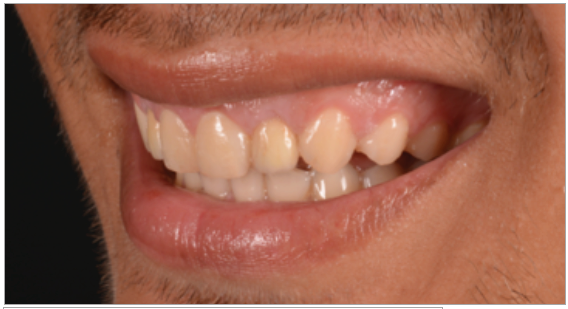

Paciente de sexo masculino de 24 años de edad, de raza mestiza, sin antecedentes sistémicos y oclusalmente estable, que fue transferido al servicio de Rehabilitación Oral del Posgrado y Especialización de la Universidad Peruana Cayetano Heredia, Lima, Perú. Recibió previamente tratamiento ortodóncico en el servicio de Ortodoncia y Ortopedia Maxilar por 6 años. Al examen intraoral presentó agenesia de las piezas 12 y 22 con evidencia de defectos óseos, presenta fenotipo periodontal grueso (figura 1). Al examen radiográfico se observa disminución generalizada de las raíces (Rizomicri), presenta ensanchamiento del ligamento periodontal generalizado (figura 2). Para el plan de trabajo para el diagnóstico se obtuvieron modelos de estudio primario, realizando el encerado para la planificación del tratamiento del sector anterosuperior. Al análisis tomográfico se evidenció poca disponibilidad ósea, motivo por el cual se planificó dos injertos en bloque de mentón con hueso particulado y plasma rico en plaquetas previo a la colocación de implantes dentales (figura 3 y figura 4). Pasado el tiempo de osteointegración (6 meses) se colocaron dos implantes Strong WS Cono Morse (SIN®, Sao Paulo, Brasil) de 3.5 mm x 11 mm. En la segunda fase, se confeccionaron provisionales de acrilico termocurado Vitalloy® (Vitacryl; A. Tarrillo Barba S.A., Lima, Perú) para el manejo de los tejidos blandos a nivel de las piezas 12 y 22, los cuales estuvieron fijados a un cilindro provisional de titanio (SIN®, Sao Paulo, Brasil) atornillado al implante, verificando la adaptación de este al implante mediante una radiografía periapical (figura 5). El cilindro fue recortado dando una altura de 6 mm, los provisionales fueron agujerados en el medio (figura 6), de tal forma que el cilindro calce en el medio del espacio edéntulo, se cubrió la entrada del cilindro con teflón (Golfo USA®) y se capturó el cilindro con acrílico de autocurado Duralay color 62 (Reliance Dental Manufacturing LLC, Illinois USA) (figura 7). Después del acrilizado se retiró el provisional, en la parte cervical se realizó un incrementó con resina fluida (Filtek™ Z350XT Flow - 3M ESPE Dental Products. St. Paul, Minnesota, USA) formando el contorno crítico a 2mm por debajo del zenit de los incisivos centrales de tal manera que entre los zenits de los incisivos centrales, laterales y caninos formen una zona triangular. El contorno subcrítico se realizó de forma convexa (figura 7 y figura 8). Se finalizó con el acabado y pulido del provisional con gomas de grano grueso (gris) y grano fino (verde) (Politip, Ivoclar-Vivadent; Schaan, Liechtenstein). Se manejó la conformación de los tejidos blandos en 2 citas mediante la adición por capas de resina compuesta (Filtek™ Z350 - 3M ESPE Dental Products. St. Paul, Minnesota, USA) a nivel del contorno crítico y subcrítico a las 2 semanas y 4 semanas de la instalación del provisional (figura 9 y figura 10). Se logró conformar las papilas interdentales, el contorno crítico y subcrítico observando que los tejidos se encontraran estables, sin inflamación, con el color de la encía igual a la encía adyacente; todo esto nos indicó que se podía realizar la impresión definitiva. La instalación final se realizó con coronas metal cerámicas cementadas (figura 11 y figura 12).